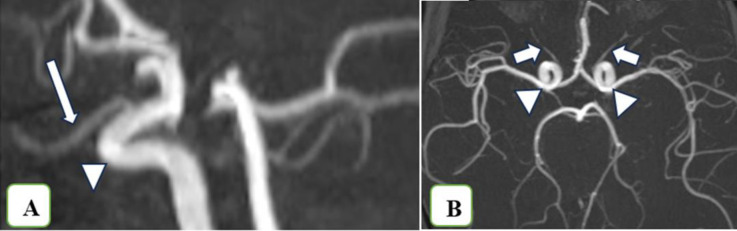

Results: Overall, 62 publications were reviewed. The ophthalmic artery branches into several arteries-the central retinal artery supplies the retina, whereas the posterior ciliary arteries supply the posterior choroid and optic nerve. The anterior ciliary arteries mainly supply the conjunctiva, sclera, ciliary body, and iris. Extraocular muscles receive their primary blood supply from the muscular branches of the ophthalmic artery, lacrimal artery, and infraorbital artery. The lacrimal gland is perfused by the lacrimal artery. The eyelids receive blood from both the internal and external carotid arteries. The superficial vascular network of the medial eyelid skin is established primarily through anastomoses between the branches of the internal carotid artery. The superficial vascular network of the lateral upper and lower eyelids is primarily derived from branches emanating from the superficial temporal artery (a branch of the external carotid artery) and the lacrimal artery. Venous drainage follows a complex pathway, beginning with the central retinal vein and the vortex veins, then draining into the ophthalmic veins, and finally into the internal jugular vein.